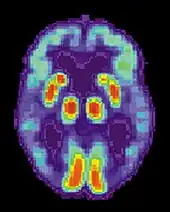

PET scan of the brain of a person with AD showing a loss of function in the temporal lobe

Alzheimer's disease is usually diagnosed based on the person's medical history, history from relatives, and behavioural observations. The presence of characteristic neurological and neuropsychological features and the absence of alternative conditions is supportive.[116][117] Advanced medical imaging with computed tomography (CT) or magnetic resonance imaging (MRI), and with single-photon emission computed tomography (SPECT) or positron emission tomography (PET) can be used to help exclude other cerebral pathology or subtypes of dementia.[118] Moreover, it may predict conversion from prodromal stages (mild cognitive impairment) to Alzheimer's disease.[119]